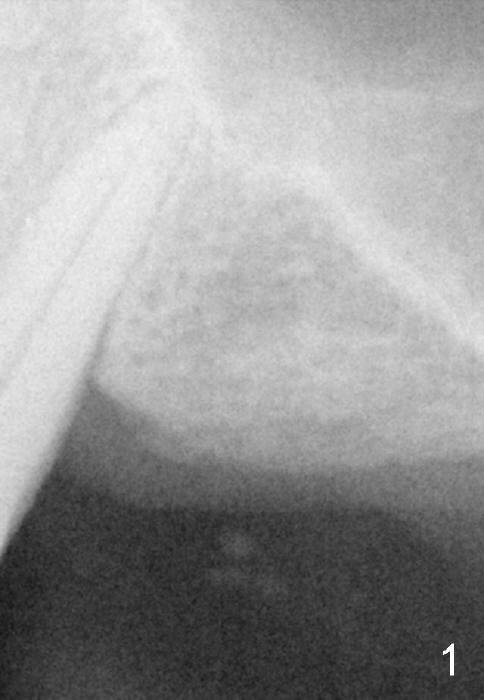

Fig.1: preop; Fig.4: 3.5x11 mm drill; Fig.5': 4.5x11 mm tap; Fig.6: 4.5x11 mm implant. Red line: original mesial apical outline of osteotomy. It shows that it is possible to change trajectory at late stage of osteotomy by changing angulation and position of burs, paying attention of orientation of tap and implant while inserting them.